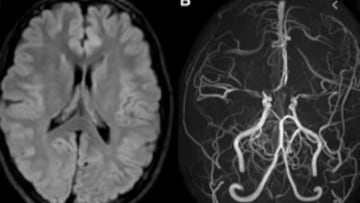

El término “Moyamoya” proviene del japonés y significa “nube de humo”, una descripción gráfica del aspecto que presentan, en angiografías y resonancias magnéticas, los vasos sanguíneos frágiles que los pacientes desarrollan para compensar la estenosis de las arterias cerebrales. Esta enfermedad cerebrovascular crónica y rara es especialmente prevalente en Asia, donde la incidencia es significativamente mayor que en los países occidentales.

La característica principal de la enfermedad es el estrechamiento progresivo de las arterias pre cerebrales y cerebrales, particularmente las carótidas y sus ramas, lo que puede culminar en la obstrucción total de estas arterias. Esto puede resultar en accidentes cerebrovasculares, isquémicos o, menos frecuentemente, hemorrágicos, afectando incluso a personas jóvenes. En Japón, la incidencia de Moyamoya es de 0.54 casos por cada 100,000 habitantes, mientras que en Occidente es mucho menor, variando entre 0.047 y 0.086 casos por 100,000 habitantes. Además, en Asia se ha identificado una fuerte predisposición genética asociada al gen Rnf213, un hallazgo que no se ha replicado en Occidente.